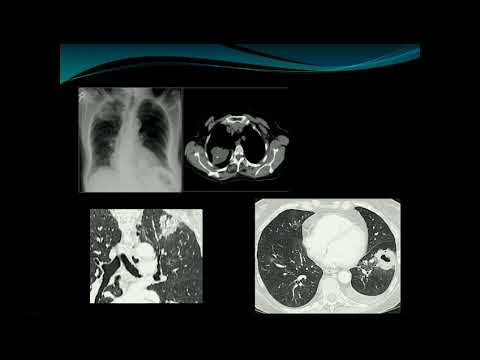

Evaluation and Management of Patients With Pulmonary Nodules